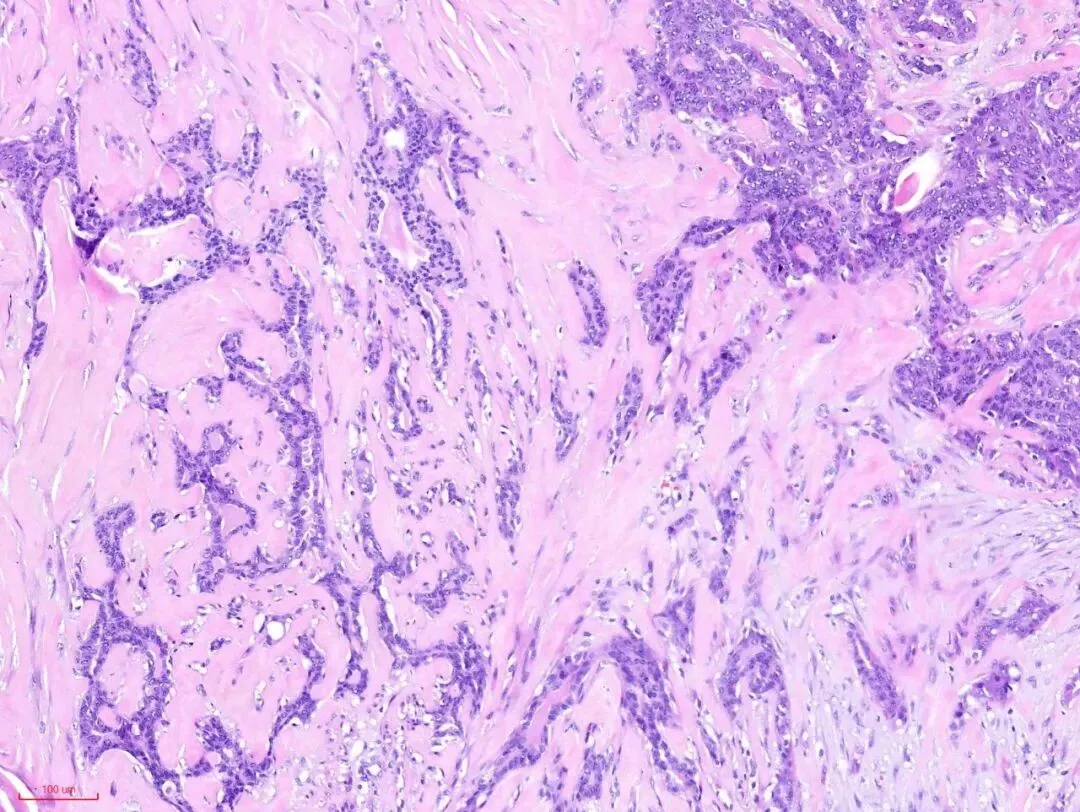

这是低倍镜下的一张图片,纤维结缔组织大量的增生→会挤压包裹其中的腺体→被挤压的腺体扭曲、变形、拉长。如下图:

在没有粉染的硬化的间质旁边,似乎可以看到小叶的特化性间质。

再观察腺体,可见到受挤压的腺体还保留着腺上皮(蓝染的)和肌上皮(粉染的或透明的)的双层结构。